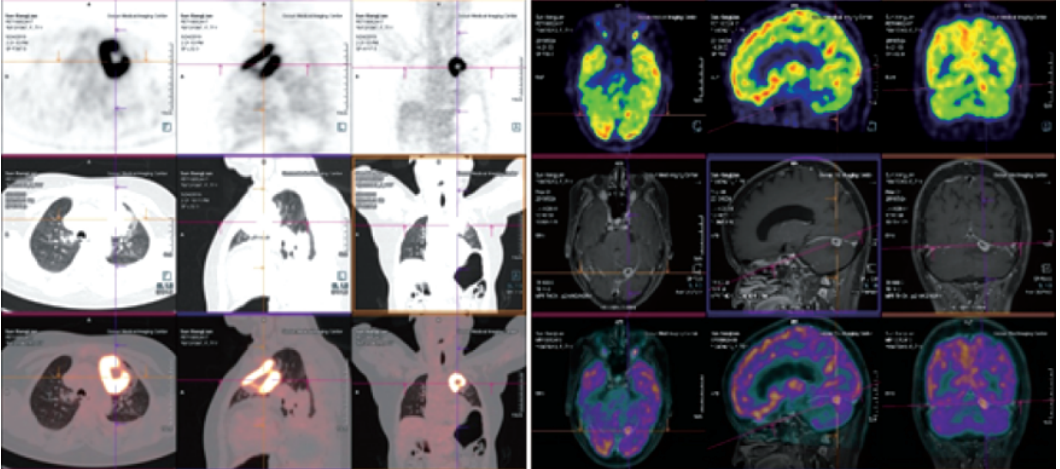

Biograph mCT.S 西門子PET/CT(正電子發(fā)射及計算機斷層掃描系統(tǒng))

★PET/CT在全身腫瘤的早期篩查、早期診斷、良惡性鑒別、惡性腫瘤的分期、分級、尋找腫瘤原發(fā)病灶、評估療效及監(jiān)測腫瘤復(fù)發(fā)等方面具有重要價值。

本設(shè)備圖像重建矩陣可達(dá)400×400,其分辨率達(dá)到毫米級;提供精細(xì)器官細(xì)節(jié)顯示,對病灶提供精確的可重復(fù)定量分析;顯著提高微小病灶的檢出和確診率。

PET/CT是通過血管內(nèi)注射示蹤劑,采用動態(tài)連續(xù)掃描全身,動態(tài)數(shù)據(jù)分析,跟蹤檢查精準(zhǔn)定位,全身病變無處遁形。

本設(shè)備采用流式掃描技術(shù),可在3-5分鐘完成高質(zhì)量的全身掃描,具有掃描速度快、靈敏度高的特點,可快速檢查全身,提高速度和診斷效率。

案例